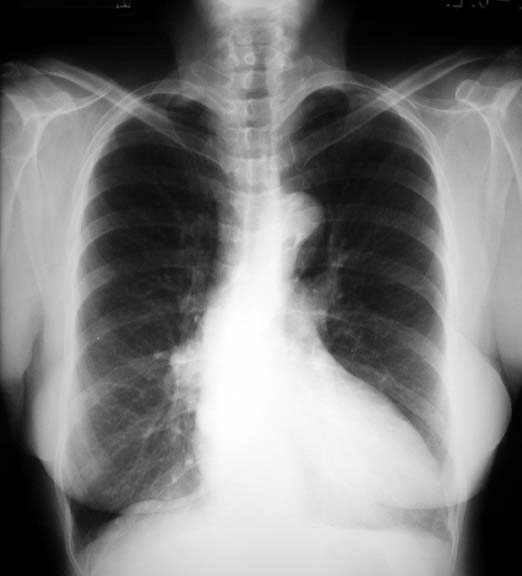

Fluid in Fissure

Phantom Tumor

Pulmonary edema

• Biconvex density

• In oblique fissure

Clearance with treatment

Other findings include:

• Displacement of right paravertebral line due to tortuous descending aorta